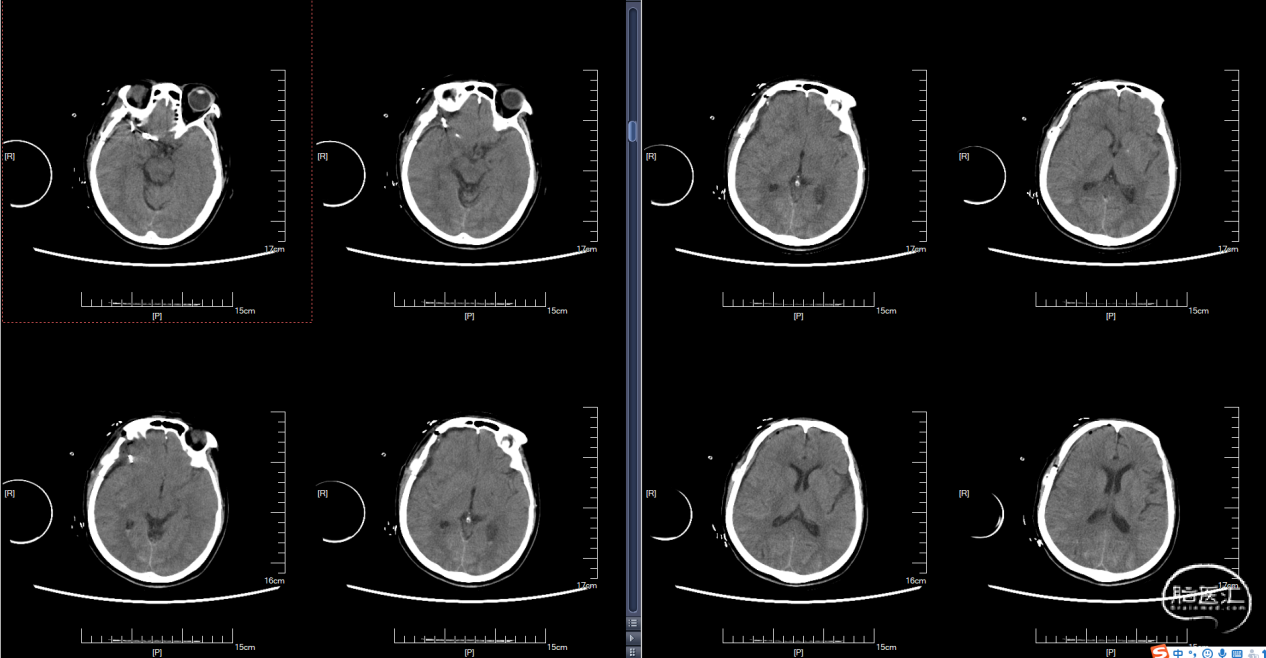

颅脑CT:蛛网膜下腔出血。

术后复查CT: